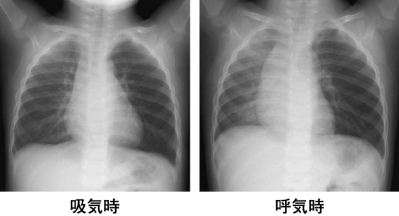

1歳10か月の男児。咳と喘鳴とを主訴に母親に連れられて来院した。昨日歩きながらピーナッツの入った菓子を食べていた時に、急にむせ込んで咳をし始めた。本日も咳が持続し喘鳴が出現したため受診した。体温 36.7 ℃。脈拍 108/分、整。 呼吸数 30/分。SpO2 98 %(room air)。吸気時と呼気時の胸部エックス線写真を示す。